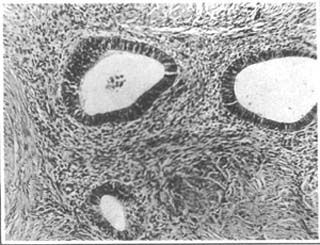

當(dāng)子宮內(nèi)膜和間質(zhì)侵入到子宮肌層時稱為子宮肌腺癥。痛經(jīng)是子宮肌腺癥的最主要的癥狀。因?yàn)樵陆?jīng)期,異位灶內(nèi)的子宮內(nèi)膜與子宮內(nèi)的內(nèi)膜組織同樣發(fā)生出血和有大量前列腺素F2α的釋放,刺激全身平滑肌痙攣,引起子宮輸卵管痙攣和活動異常,同時使子宮致密肌層出血,就引起劇烈的,甚至比子宮內(nèi)膜異位癥更劇烈的痛經(jīng),而且逐月加重,很多患者即使服用止痛藥都無法緩解,甚至更嚴(yán)重的影響到日常生活和工作。通常這種時候,在藥物都無法緩解的情況下,西醫(yī)就只能是采取手術(shù)切除子宮了。